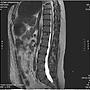

[問題]想請教手腳酸麻是否需重照MRI?

[ Doctor-Info ]